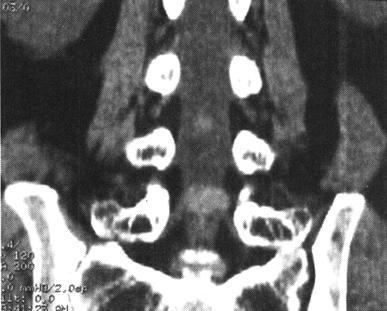

CT在脊柱脊髓损伤中应用很广泛,横断面成像是诊断脊椎骨结构创伤的主要手段,它可显示X线平片不易显示的细微骨折和小关节脱位,并能够很好地显示骨性椎管的情况,可为评价脊髓受压情况提供重要的影像学信息。螺旋CT扫描技术可对患者进行快速连续多部位成像,并支持多平面及三维成像。因而CT扫描对理解脊柱复杂解剖部位,发现细微病变有十分重要的临床意义(图7-4至图7-6)。甚至明显侧弯变形脊柱的冠状面重建亦可通过严格按照脊柱弯曲度改进的软件而获得。单纯轴位扫描很容易漏诊与CT断层面平行的骨折,例如,发生在齿突基部和胸腰水平的创伤,在横断位扫描中不能显示横断水平的骨折线,但在高质量的冠状、矢状和三维的重建图像中显示良好(图7-7至图7-10)。

图7-5 多排螺旋CT重建:冠状面重建,显示硬膜囊和双侧神经根袖